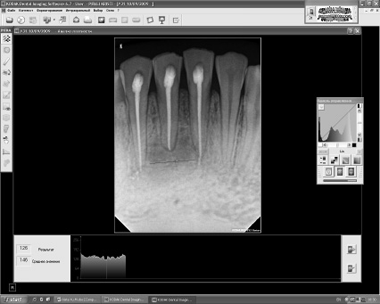

Пациентка Л. 20 лет, обратилась в клинику челюстно-лицевой хирургии б-цы “Мурацан” 17.03.2009 г. с жалобами на припухание мягких тка-ней в области подбордка и болезненность нижних фронтальных зубов. Отмечала травму, полученную в области подбородка в детсве. При осмотре -внешне асимметрия лица за счет припухлости мягких тканей в области подбородка, кожа над припухлостью слабо гиперемирована. Со стороны полости рта- отек и гиперемия слизистой в области переходной складки нижних фронтальных зубов. Фронтальные зубы интактны, перкуссия болезнена. Рентгенологическое исследование на RVG Kodak 6100 радиовизиогра- фе – показал дефект кости с четкими контурами под корнями 31.41.42 зубов, размерами 19x15, со средней плотностью кости 74УЕСЦ (условных единиц серого цвета): max-98 УЕСЦ, тт-53УЕСЦ (рис.За). После клинико-рентгенологического обследования был по-ставлен диагноз - травматическая радикулярная ки-ста подбородочного отдела нижней челюсти.

14.04.2009г. под местным обезболиванием проведена депульпация зубов, апексы которых находились в зоне кисты и операция - цистэктомия с заполнением костного дефекта по вышеописанной методике. Послеоперационный период протекал гладко, швы удалялись на 7-е сутки после оперции. При контрольном осмотре через месяц после операции- слизистая розового цвета, отечности мягких тканей не наблюдалось. При RVG денситометрии через 1мес после операции среднее значение плотности кости составляло 110 УЕСЦ: с max-132 УЕСЦ, min-97 УЕСЦ (рис.3Б). На 3-м же мес наблюдалось полное восстановление дефекта, с образованием органоти-пичной кости, с аналогичной изоплотностью с ма-теринской. Среднее значение плотности составляло 146 УЕСЦ: тах-172 УЕСЦ, тт-126 УЕСЦ.